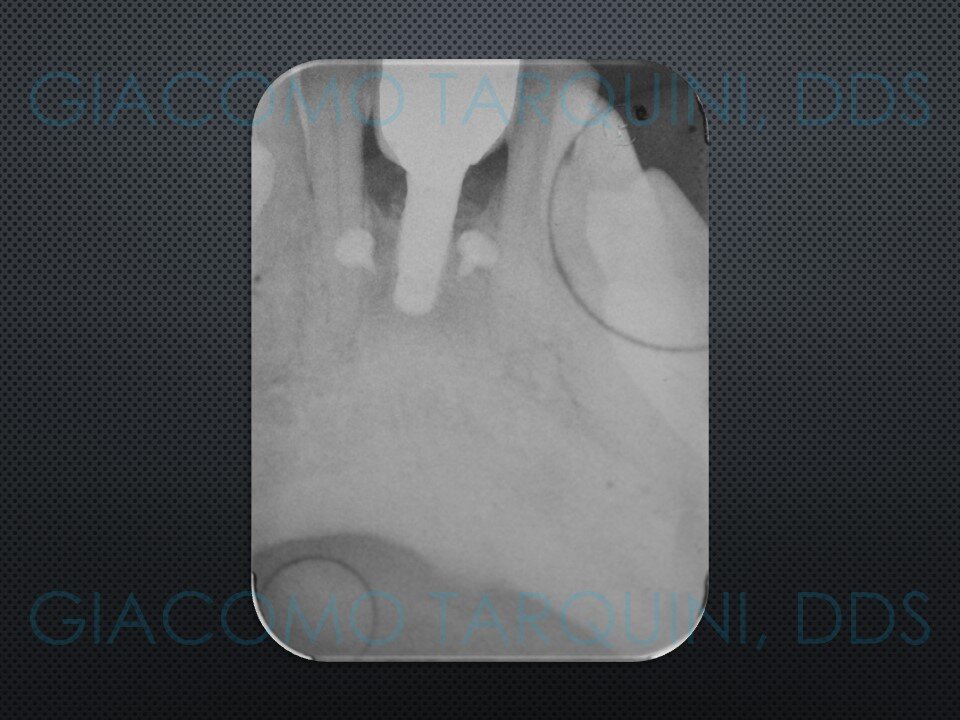

- Sondaggio e valutazione radiografica peri-implantare

- Rientro chirurgico e follow-up radiografico per valutare il grado di rigenerazione ossea ottenuta

Ho aggiornato il caso clinico con ricostruzione Panorex + sondaggi parodontali pre e post-operatori.